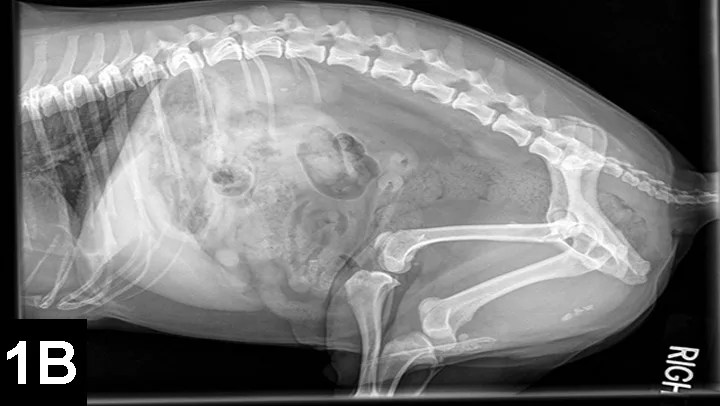

Figure 1B. Tucked lateral radiograph showing additional CaOx urethroliths

Older dogs and cats (8–12 years) are most commonly affected by CaOx uroliths, and concurrent urinary tract infection appears to be rare. CaOx uroliths are typically the most radioopaque of all uroliths and usually easily observed on plain film radiographs (Figures 1 and 2).